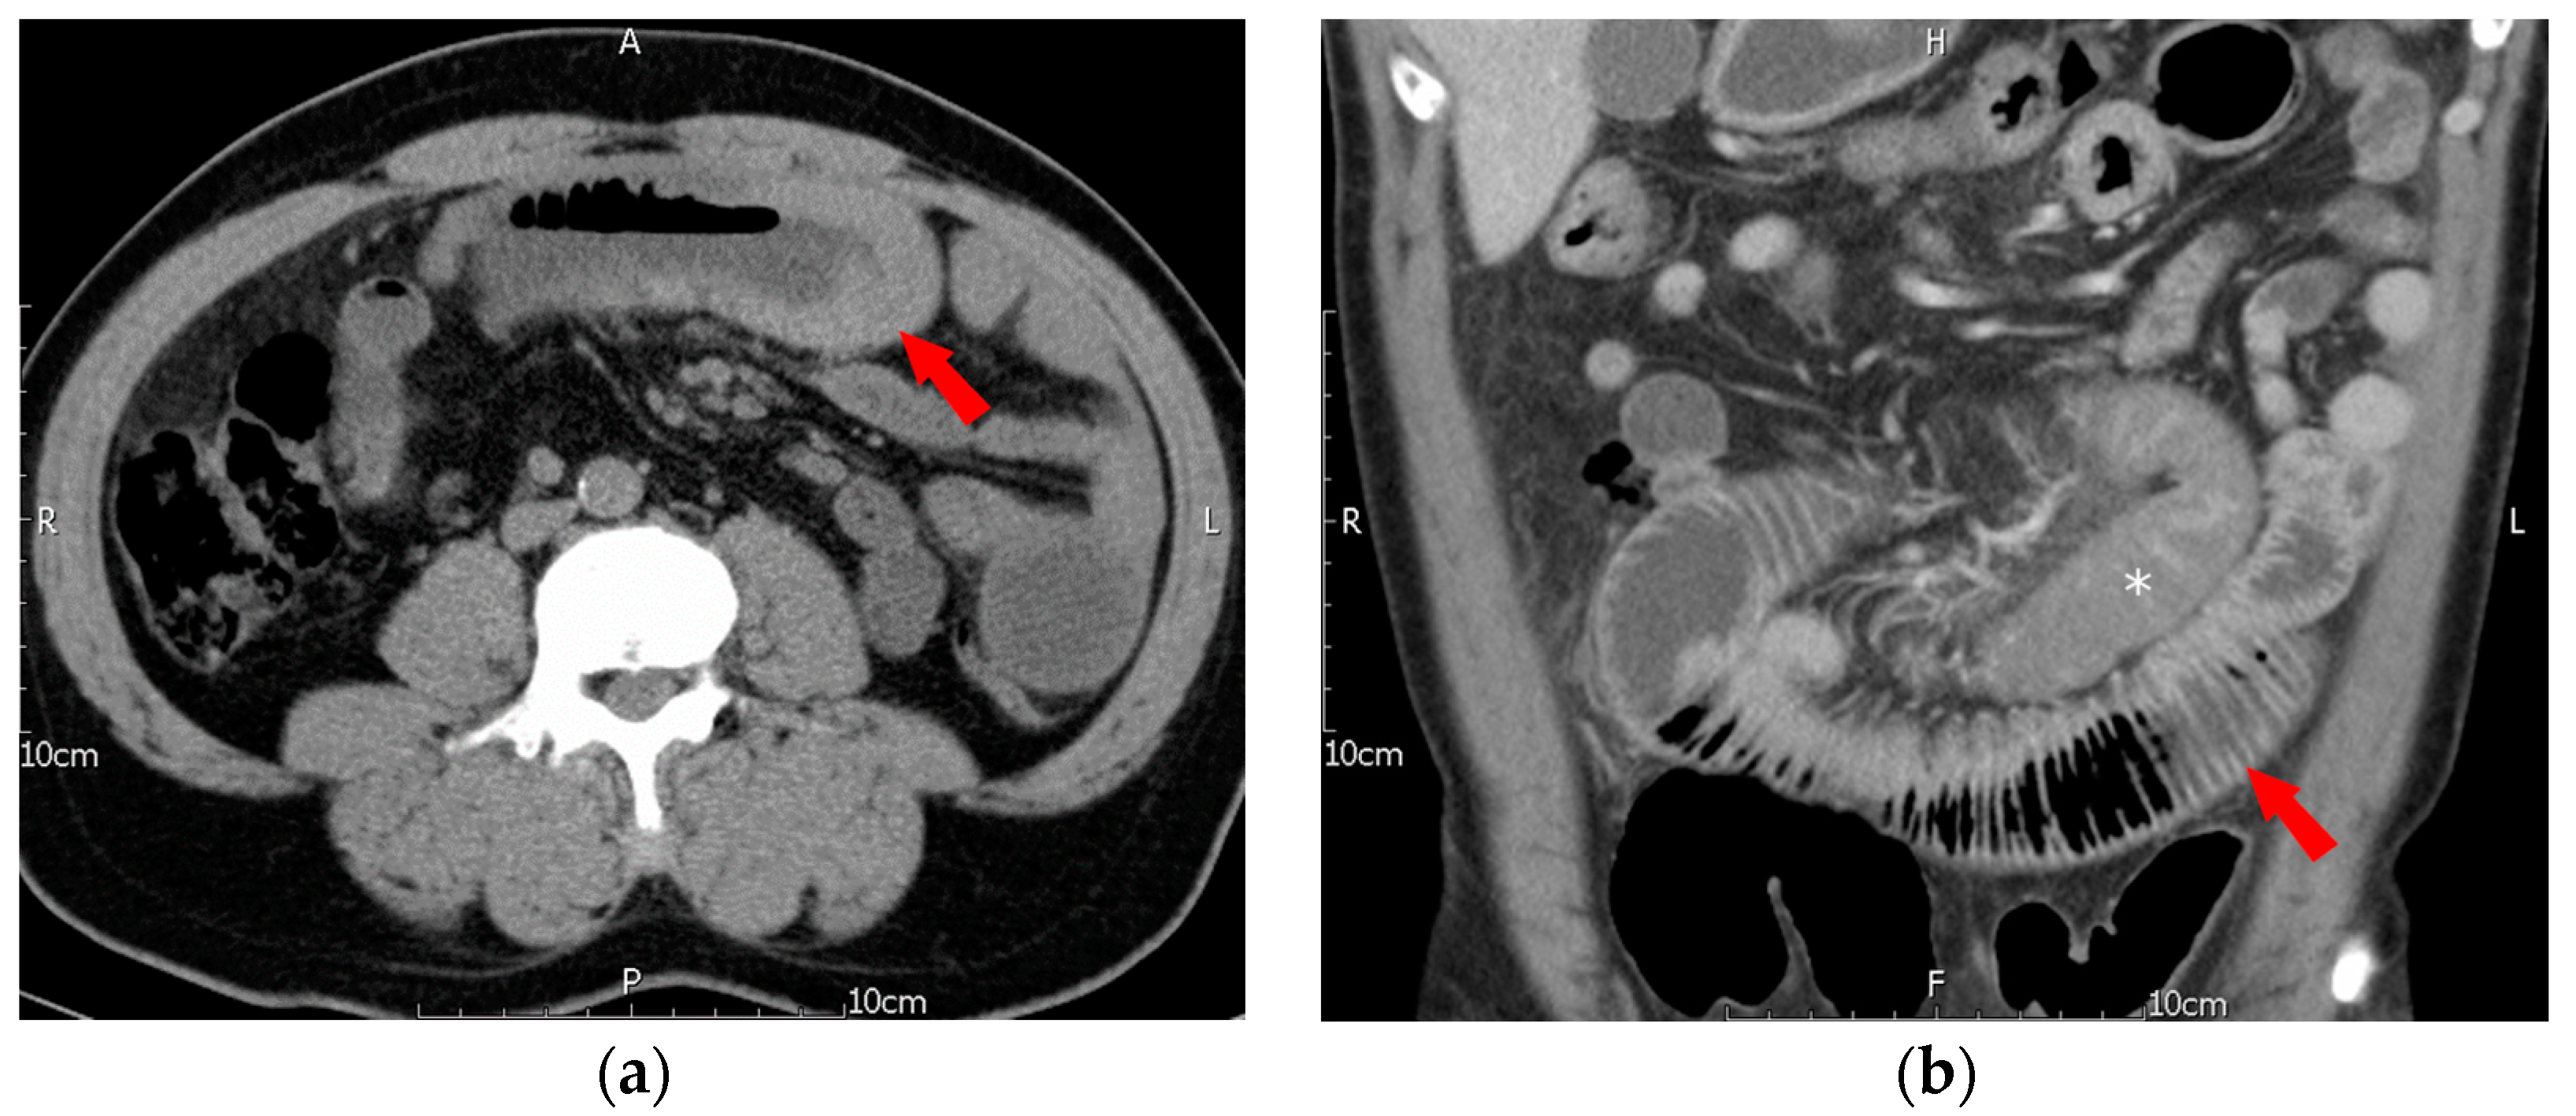

However, just two and a half months later, in early September 2019, he presented once again at our emergency department with similar symptoms. This time, the chief complaint was lower and periumbilical abdominal pain that had persisted for 3 days, along with nausea and decreased appetite. The patient had not passed stool for 3 days and had not experienced fever, diarrhea, or tarry or bloody stool recently. Physical examination identified periumbilical tenderness and rebound pain. Lab data indicated leukocytosis (WBC: 13,690/µL) with neutrophil predominance and an elevated CRP level of 6.19 mg/dL. The patient’s Hb level was 15.0 g/dL, and his platelet count was 418 × 103/µL. Although the PT/INR was normal at 1.04, the aPTT was prolonged at >180.0 s (control: 32–45 s). An abdominal CT revealed segmental wall thickening at the midjejunum, compatible with intramural hematoma, causing partial obstruction of the bowel, dilatation of the proximal jejunum and stomach, indicating mechanical ileus. The involved segments of the hematoma differed from those in the previous episode (Figure 2).

Figure 2.

Second episode of intramural hematoma of jejunum. (a) Axial non-contrast CT showed segmental thickening of the midjejunum with diffuse hyperdensity, indicating intramural hematoma (arrow), (b) coronal reformatted contrast-enhanced CT showed intramural hematoma (*) of the midjejunum and marked dilatation of the proximal jejunum, indicating mechanical ileus (arrow).